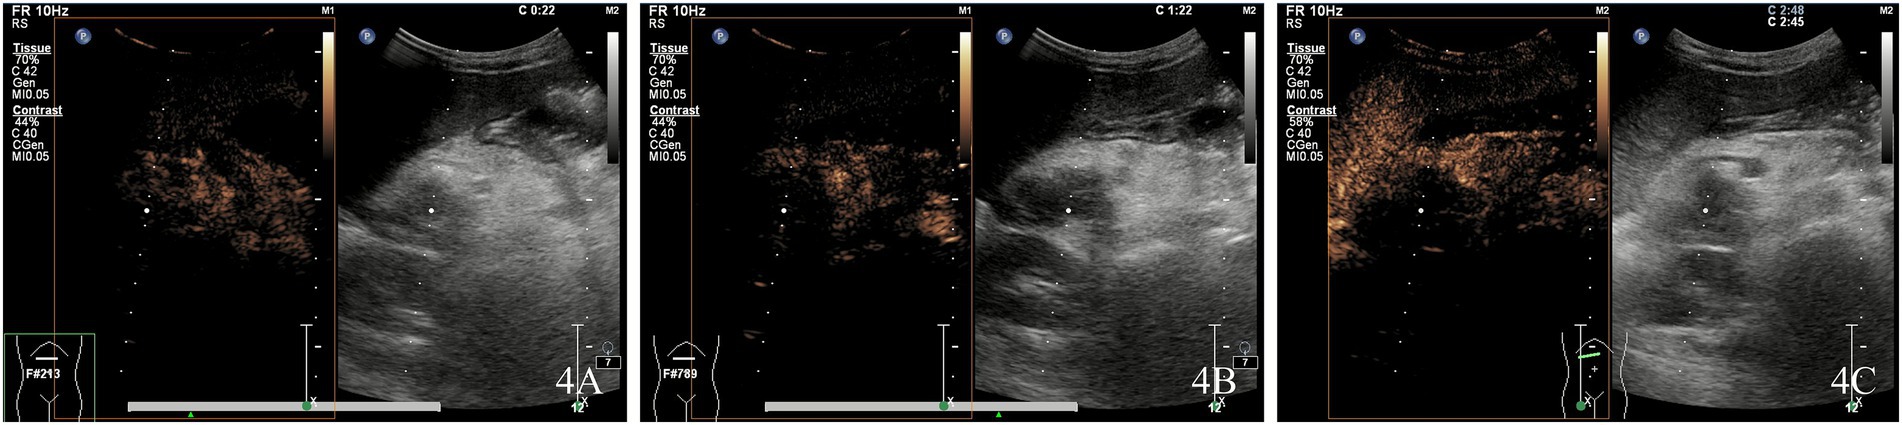

Ultrasound examination revealed a hypoechoic mass in the pancreatic head, measuring ~4.0 × 2.9 × 3.5 cm, with unclear borders and irregular morphology. Punctate blood flow signals (Adler blood flow grade 2) were observed within the lesions (Figure 3). Enhancement of the pancreatic parenchyma was observed 19 s after contrast injection. The lesion exhibited rapid, inhomogeneous hypoenhancement at 22 s after contrast administration and consistently maintained this inhomogeneous hypoenhancement. The imaging findings showed a hypoenhanced lesion in the arterial phase (Figure 4A) and lower enhancement in the portal venous phase (Figure 4B). By 80 s, the lesion began to washout, with nearly complete washout observed in the late phase (Figure 4C). This suggested the presence of a tumorigenic lesion. Gray-scale ultrasound revealed that the right side of the liver was significantly reduced in size compared to the left side of the liver. High-frequency ultrasound revealed findings consistent with liver cirrhosis, including an unsmooth liver envelope and heterogeneous parenchymal echogenicity; this was supported by a markedly elevated liver stiffness measurement of 26.1 kPa on shear wave elastography. The flow velocity in the portal venous system was markedly reduced. The gallbladder wall was thickened (0.5 cm), and the spleen was enlarged (13.4 × 3.4 cm). These ultrasound findings indicated that the patient may have cirrhosis and portal hypertension.

Figure 4

Kaposiform hemangioendothelioma of the pancreatic head demonstrating rapid, heterogeneous hypoenhancement at 22 s post-contrast injection, with persistent heterogeneous hypoenhancement in the arterial phase (A) and progressively reduced enhancement in the portal venous phase (B). The lesion exhibited early washout starting at 80 s, with near-complete washout in the delayed phase (C).

In the present case report, the onset of the disease was occult, with skin ecchymosis and thrombocytopenia as the primary clinical manifestations, followed by recurrent pancreatitis. In this case report, KHE involved multiple organs, including the pancreatic head, liver, biliary tract, and duodenal papilla, resulting in complex clinical symptoms and imaging manifestations. Color Doppler flow imaging revealed blood flow signals in the lesions of the pancreatic head. The characteristics of KHE included inhomogeneous hypoenhancement in the arterial and portal phases, with no enhancement in the late phase. The lesion demonstrated poor enhancement across all dynamic phases on CEUS examination. These findings were consistent with the characteristics of pancreatic malignancies, such as ductal adenocarcinoma. However, sch tumors are extremely rare in children (3, 4). Based on the disease history, laboratory findings, and imaging features, we diagnosed pancreatic KHE combined with KMP.